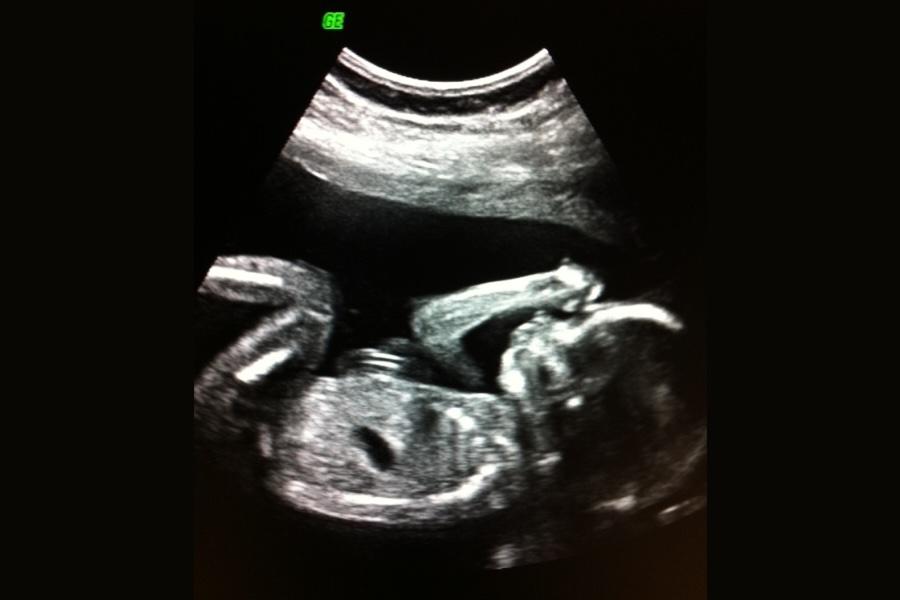

Er det liv, vi måle størrelsen og teller antal foster. Vi går også igjennom fosterets anatomi. Ultralydundersøkelsen som man planlegger nå er litt mer omfattende og man kan se de store avvikene. Foster avvikene som man oppdager så tidlig er oftest de som er de mest alvorlige og med dårligst prognose. Men ultralyden har også sine begrensninger, fosteret er i konstant utvikling og det er ikke alltid man ser avvik så tidlig i svangerskapet. Det er klare fordeler med å gjøre den ultralyden så tidlig da dette gir kvinnen og også det offentlige mer tid til å skaffe informasjon og også ta en del avgjørelser eller valg om videre oppfølgning av svangerskapet.

Mellom uke 11 og 14 skal en ultralyd gjøres. Hvorfor ultralyden gjøres først er nettopp pga av at se det er liv, telle foster og beregne svangerskapslengden. Ved funn av denne ultralydundersøkelsen kan man gå videre med en tilleggs undersøkelse.